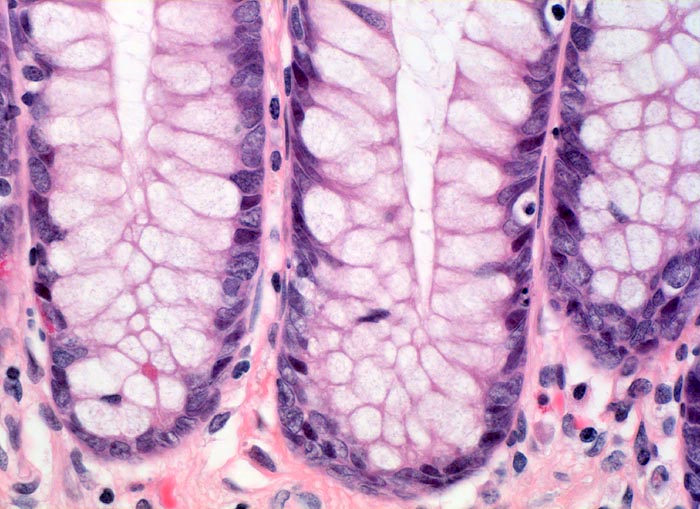

Die Colitis ulcerosa beginnt im Rektum (> 2758) und breitet sich kontinuierlich nach proximal aus. In 10% ist das gesamte Kolon (> 3364) befallen und es besteht zusätzlich eine back-wash-Ileitis im terminalen Ileum. Das Rektum ist bei unbehandelten Patienten praktisch immer befallen. Nach topischer Therapie kann das Rektum ausgespart sein und nach längerem Krankheistverlauf ist auch ein segmentaler Befall möglich. Bei fehlenden klinischen Angaben (Dauer der Erkrankung, Therapie) können diese atypischen Manifestationen diagnostische Schwierigkeiten verursachen. Makroskopisch finden sich häufig longitudinal ausgerichtete Ulzera mit Querverbindungen und Konfluenz. Residuelle Schleimhautinseln imponieren als Pseudopolypen. In der Remissionsphase ist die Schleimhaut glatt und blass, das Faltenrelief ist vergröbert und verstrichen und es finden sich häufig Granulationsgewebspolypen. Mikroskopisch findet sich je nach Entzündungsaktivität eine mehr oder weniger ausgeprägte diffuse Verdichtung des lymphoplasmazellulären Entzündungsinfiltrates mit Beimischung von Granulozyten in Form einer Kryptitis oder von Kryptenabszessen. Bei einer stark aktiven Entzündung finden sich zusätzlich Erosionen und Ulzera mit Ausdehnung der Entzündung über die Mukosa hinaus in die Submukosa oder in noch tiefere Schichten bei hochflorider Kolitis. Die Kryptenarchitektur ist gestört, die Anzahl der Krypten und der Becherzellen vermindert. In der Regeneratphase finden sich zahlenmässig reduzierte und verkürzte Krpyten mit normaler Anzahl Becherzellen. Meist bleibt eine leichte Verdichtung der Entzündungszellen in der Lamina propria bestehen.

• Abwechslungsweise oberflächliche Ulzera und pseudopolypöse Schleimhautvorwölbungen.

• Entzündungsinfiltrate in Mukosa und Submukosa.

• Unregelmässig geformte und verzweigte Krypten (Kryptenarchitekturstörung).

• Krpyten enden deutlich oberhalb der Lamina muscularis mucosae (Kryptenatrophie).

• Verminderte Schleimbildung und Becherzellverlust.

• Basal betonte Plasmozytose und Infiltrate neutrophiler Granulozyten.

• Ansammlungen neutrophiler Granulozyten in Kryptenlumina (=Kryptenabszesse) und Infiltrate von neutrophilen Granulozyten im Kryptenepithel (=Kryptitis).